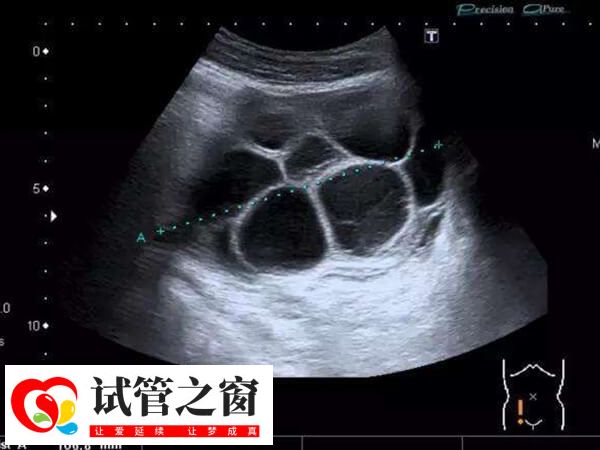

在试管治疗中,患者出现的血栓通常也会在试管移植后出现,至于试管移植第三天就出现了血栓几率是多大,对此感兴趣的可以参考下列内容:

- 由于试管移植过程中,血液凝固系统异常或血管内膜损伤导致的,因此可见出现血栓的几率相对较大,但具体因人而异;

- 一般大部分患者在试管移植第三天出现血栓几率时不大的,毕竟此时的胚胎处于着床和早期发育的阶段,暂不会增加这一风险。

因个体差异较大,试管移植第三天出现血栓几率没有固定标准,具体还要根据每个患者身体情况而定,另外,如果患者存在血液凝固性疾病、长期卧床不动、静脉血栓形成史等,那么试管移植后第三天出现血栓的几率会明显增加。